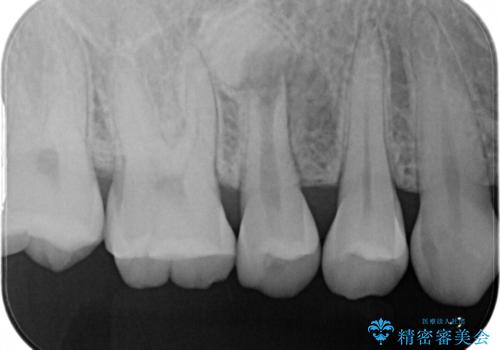

【根管治療】噛んだ時にしみる。最近になってズキズキ痛み、長引く痛みがある

担当医 河口智英